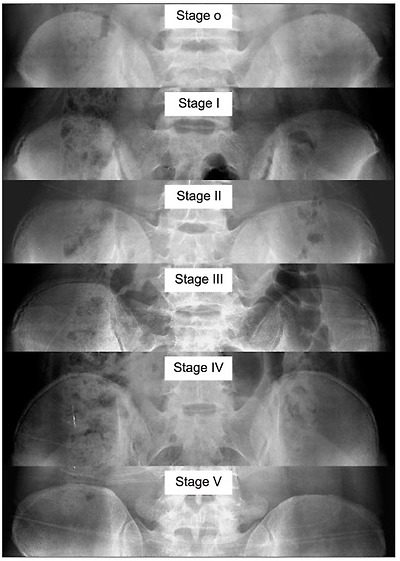

リッサーサインは、骨盤の腸骨稜(ちょうこつりょう)の骨化の程度を0から5までの6段階で評価します。

- リッサー0 : 骨化が全く見られない状態。

- リッサー1: 腸骨棘上部前部(前外側)骨端線の骨化(25%)、腸骨思春期前または思春期初期に見られる

- リッサー2:腸骨骨端線の50%骨化 、骨化は腸骨翼の半分まで広がる 、成長スパートの直前or成長スパート中に見られる

- リッサー3: 腸骨骨端線の骨化が75%。成長の鈍化を示す

- リッサー4: 100%骨化、腸骨稜との癒合なし。

- リッサー5: 腸骨骨端線が腸骨稜に癒合する。骨化が完全に終了した状態。 成長の停止を示す。

- 「 Risser 0」と「Risser 5」は、どちらもX線写真で骨化中心が見られないという点で似ています。この2つは 年齢 で区別できます。Risser 5の青年では、腸骨に成長板の開口は見られず、16歳(女性)または18歳(男性)以上になります。一方、 Risser 0の小児では 、腸骨の大部分に成長板の開口が見られます。